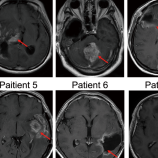

Malignant glioma is a highly fatal central nervous system malignancy with high recurrence rates. Oncolytic viruses offer potential treatment but need improvement in efficacy and safety. Here we describe a phase I, dose-escalating, single arm trial (ChiCTR2000032402) to study the safety of Ad-TD-nsIL12, an oncolytic adenovirus expressing non-secreting interleukin-12, in patients with recurrent high-grade glioma that connects with the ventricular system. Eight patients received intratumoral treatment via stereotaxis or an Ommaya reservoir, with doses ranging from 5 × 109 to 5 × 1010vp. The primary end point was to determine the maximal tolerated dose. Secondary endpoints included toxicity and anti-tumour ability. Minimal adverse events were observed at doses of 5 × 109 and 1 × 1010vp. Grade 3 seizure was observed in two patients from Cohort 3 (5 × 1010vp). Therefore, the maximum tolerated dose was determined to be 1 × 1010vp. Four patients developed hydrocephalus during follow-up. Among them, symptoms in two patients were relieved after placement of a ventriculo-peritoneal shunt, and the other two only showed ventriculomegaly on MRI scan without neurological deterioration. Complete response (according to Response Assessment in Neuro-Oncology Criteria) in one patient, a partial response in one patient and post-treatment infiltrations of CD4+ and CD8 + T cells into the tumour were documented during this trial. In conclusion, Ad-TD-nsIL12 has demonstrated safety and preliminary efficacy in patients with recurrent high-grade glioma. Oncolytic viruses have been tested in patients with malignant glioma, however clinical efficacy remains limited. Here the authors report the results of a phase I trial of Ad-TD-nsIL12, an oncolytic adenovirus expressing a mutant (non-secreting) form of IL12, in patients with high-grade glioma.